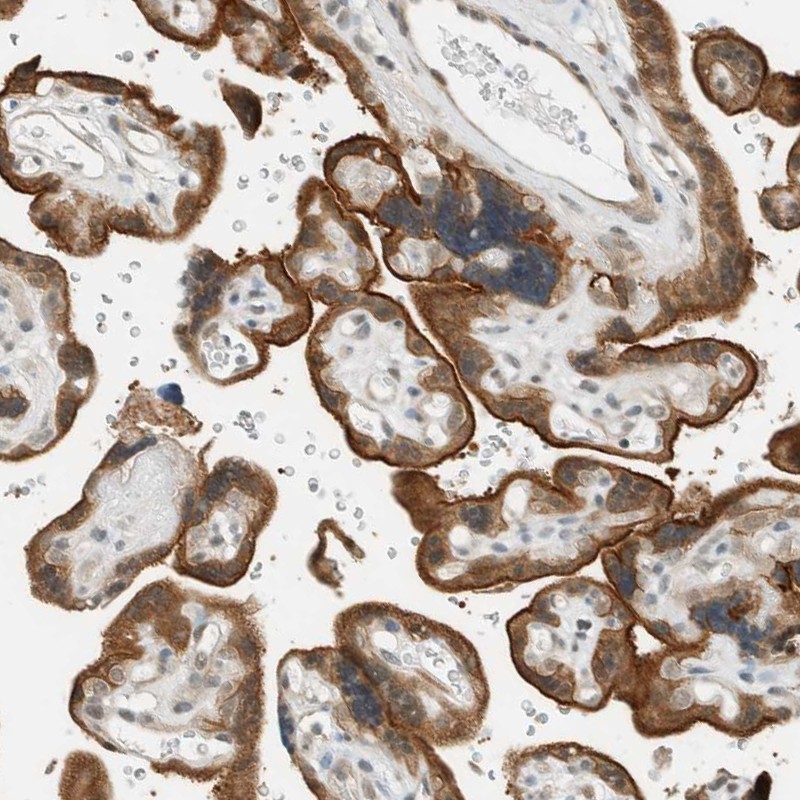

Immunohistochemical staining of human placenta shows strong cytoplasmic positivity in trophoblastic cells.